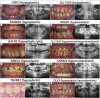

Amelogenesis imperfecta (AI) is a heterogeneous group of genetic rare diseases disrupting enamel development (Smith et al., Front Physiol, 2017a, 8, 333). The clinical enamel phenotypes can be described as hypoplastic, hypomineralized or hypomature and serve as a basis, together with the mode of inheritance, to Witkop's classification (Witkop, J Oral Pathol, 1988, 17, 547-553). AI can be described in isolation or associated with others symptoms in syndromes. Its occurrence was estimated to range from 1/700 to 1/14,000. More than 70 genes have currently been identified as causative. Objectives: We analyzed using next-generation sequencing (NGS) a heterogeneous cohort of AI patients in order to determine the molecular etiology of AI and to improve diagnosis and disease management. Methods: Individuals presenting with so called "isolated" or syndromic AI were enrolled and examined at the Reference Centre for Rare Oral and Dental Diseases (O-Rares) using D4/phenodent protocol (www.phenodent.org). Families gave written informed consents for both phenotyping and molecular analysis and diagnosis using a dedicated NGS panel named GenoDENT. This panel explores currently simultaneously 567 genes. The study is registered under NCT01746121 and NCT02397824 (https://clinicaltrials.gov/). Results: GenoDENT obtained a 60% diagnostic rate. We reported genetics results for 221 persons divided between 115 AI index cases and their 106 associated relatives from a total of 111 families. From this index cohort, 73% were diagnosed with non-syndromic amelogenesis imperfecta and 27% with syndromic amelogenesis imperfecta. Each individual was classified according to the AI phenotype. Type I hypoplastic AI represented 61 individuals (53%), Type II hypomature AI affected 31 individuals (27%), Type III hypomineralized AI was diagnosed in 18 individuals (16%) and Type IV hypoplastic-hypomature AI with taurodontism concerned 5 individuals (4%). We validated the genetic diagnosis, with class 4 (likely pathogenic) or class 5 (pathogenic) variants, for 81% of the cohort, and identified candidate variants (variant of uncertain significance or VUS) for 19% of index cases. Among the 151 sequenced variants, 47 are newly reported and classified as class 4 or 5. The most frequently discovered genotypes were associated with MMP20 and FAM83H for isolated AI. FAM20A and LTBP3 genes were the most frequent genes identified for syndromic AI. Patients negative to the panel were resolved with exome sequencing elucidating for example the gene involved ie ACP4 or digenic inheritance. Conclusion: NGS GenoDENT panel is a validated and cost-efficient technique offering new perspectives to understand underlying molecular mechanisms of AI. Discovering variants in genes involved in syndromic AI (CNNM4, WDR72, FAM20A … ) transformed patient overall care. Unravelling the genetic basis of AI sheds light on Witkop's AI classification.

Figures